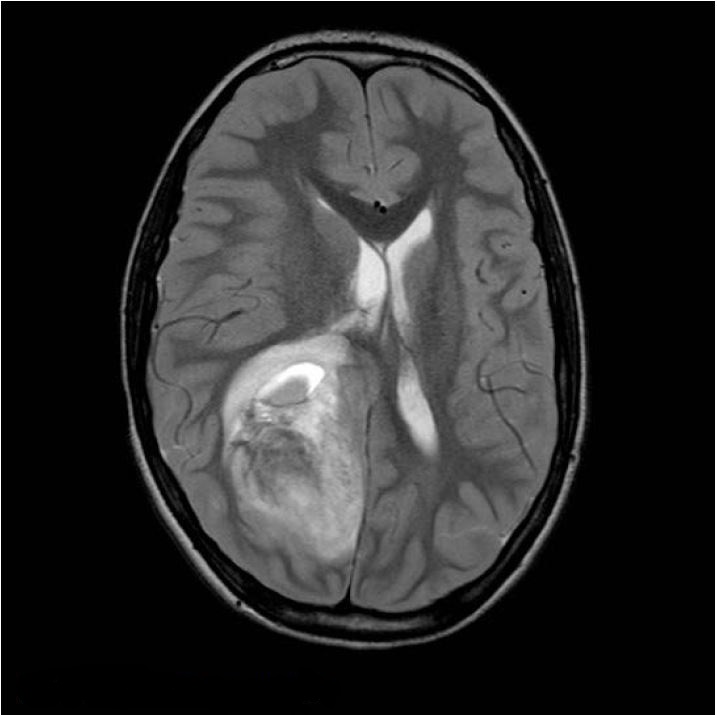

При неврологічному огляді виявлено двобічний набряк зорового нерву, двобічний парез 6-го черепного нерва, геміанопсію. Його одразу направили на МРТ. Було виявлено велике пухлинне утворення, частково геморагічне, у правій тім’яній ділянці з значним мас-ефектом (рис. 1 і 2).

Рисунок 2 T1WI + GD, перше сканування